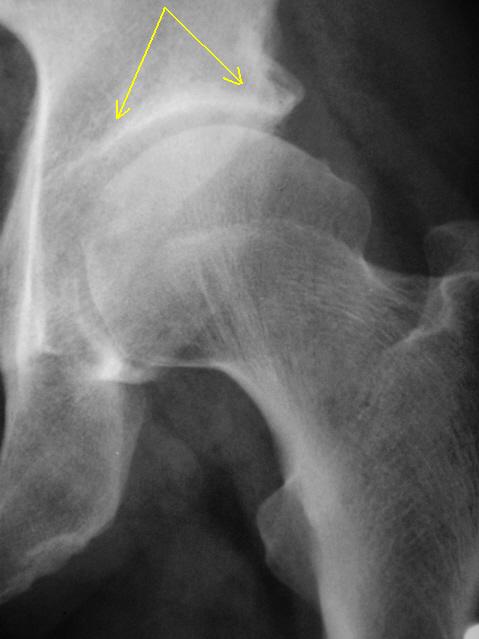

Я думаю, что деформирующий артроз левого тазобедренного сустава, однозначно имеет место быть. Об этом свидетельствует и деформация суставной поверхности головки бедренной кости - "уплощение", "двугорбость" или незначительно выраженная "грибовидная" деформация, по сравнению с головкой противоположной стороны.

Также четко определяется наличие субхондрального склероза по верхнему наружному контуру вертлужной впадины.

О функциональной перегрузке левого тазобедренного сустава свидетельствует также перестройка архитектоники шейки бедренной кости. В медиальном отделе шейки бедренной кости, с дальнейшим распространением на головку определяется сгущение "костных балок и их утолщение", по сравнению с латеральным отделом шейки - по всей видимости, компенсаторный процесс, в результате перераспределения нагрузки?

Как быть с "формальными признаками" деформирующего артроза, согласно всем классификациям, хоть Келгрену, хоть Н.С. Косинской, где первым и самым фундаментальным признаком является "сужение суставной щели", где акцентировано, что "деформирующего артроза без сужения суставной щели не бывает". В "нашем случае" со стороны деформирующего артроза суставная щель не только не сужена, но даже и расширена.

Первое, что бросилось в глаза - это некоторое уплощение головки левого бедра, так называемая, двугорбость головки, небольшая латеропозиция головки (расширение р-суставной щели в нижнемедиальном отделе). Такую форму головок встречаю в исходе болезни Пертеса. В детстве не было болезни Пертеса у больного? Ну, и изменения в обл. лонного сочленения.